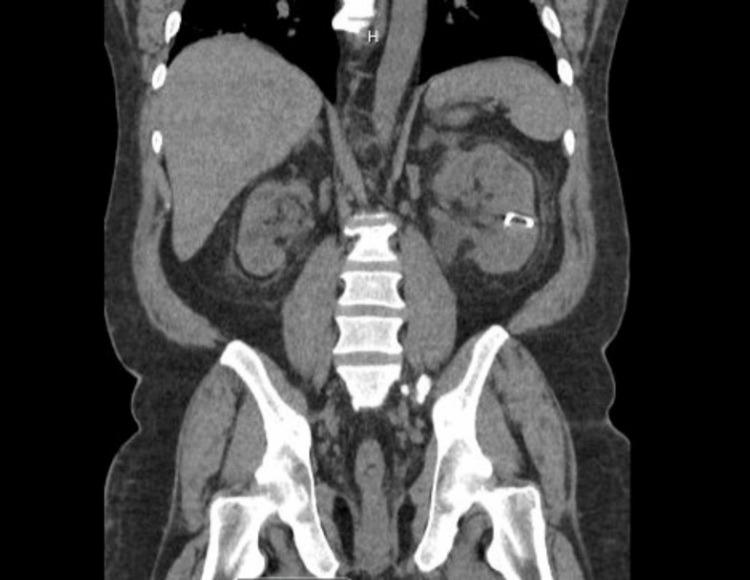

Inguinoscrotal hernias involving the urinary bladder are exceedingly rare, constituting a small subset of inguinal hernias. We present a case of a 47-year-old male with long-standing scrotal enlargement and obstructive uropathy due to complete herniation of the bladder with ureteric involvement. Diagnostic imaging confirmed the condition. Following an open laparotomy, the bladder was reduced, and a modified Bassini technique with orchiopexy was used for repair. Recurrence of the inguinoscrotal hernia with evidence of the bladder in the scrotal sac required additional surgery. This case underscores the rarity, diagnostic complexity, and potential complications of inguinoscrotal bladder hernias. Specialized surgical techniques and a multidisciplinary approach are crucial for successful management, especially in cases of complete bladder herniation. Future considerations should include innovative approaches to enhance primary repair outcomes for extensive hernias involving the bladder.

累及膀胱的腹股沟阴囊疝极为罕见,是腹股沟疝中的一小部分。我们报告一例47岁男性,因膀胱完全疝出并累及输尿管,长期阴囊肿大并患有梗阻性尿路病。诊断性影像学检查证实了病情。在进行开放剖腹手术后,将膀胱回纳,并采用改良的巴西尼技术加睾丸固定术进行修复。腹股沟阴囊疝复发且阴囊囊中出现膀胱迹象,需要再次手术。该病例凸显了腹股沟阴囊膀胱疝的罕见性、诊断复杂性和潜在并发症。专门的手术技术和多学科方法对于成功治疗至关重要,尤其是在膀胱完全疝出的病例中。未来的考虑应包括创新方法,以提高涉及膀胱的广泛性疝的一期修复效果。